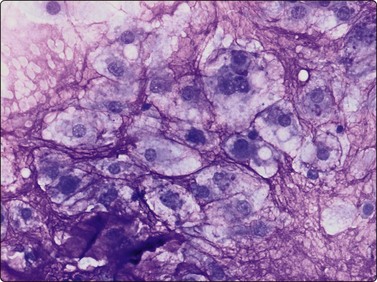

Langerhans cell histiocytosis presents as lytic and often well-defined lesions. Most cases are seen in children. The lesions may be solitary (most cases) or multiple. The long bones (femur and humerus) and the skull are the most common sites in children, and the pelvic bones and ribs in adults. The cytological pattern of Langerhans cell histiocytosis is fairly characteristic and may be diagnostic. The typical histiocytes have moderately larger and paler nuclei than those seen in common inflammatory processes. Generally reniform, the nuclei have a distinct irregular and folded outline (Fig. 16.10A). Coffee-bean nuclei has been reported to be typical of this lesion (Fig. 16.10B). The chromatin is entirely bland and nucleoli small. The cytoplasm is abundant and pale and has fairly well-defined borders. It is often vacuolated. In exceptional cases the Langerhans cells may show signs of phagocytosis. Multinucleated cells of similar type are commonly present. These can be quite large and may resemble osteoclasts in wet-fixed smears.

image image

Fig. 16.10 Langerhans cell histiocytosis (eosinophilic granuloma)

(A) Lytic bone lesion, many histiocytes with irregular reniform pale nuclei, some eosinophils (H&E, IP); (B) Coffee-bean nuclei have been reported to be typical of this lesion (H&E, HP, Oil)